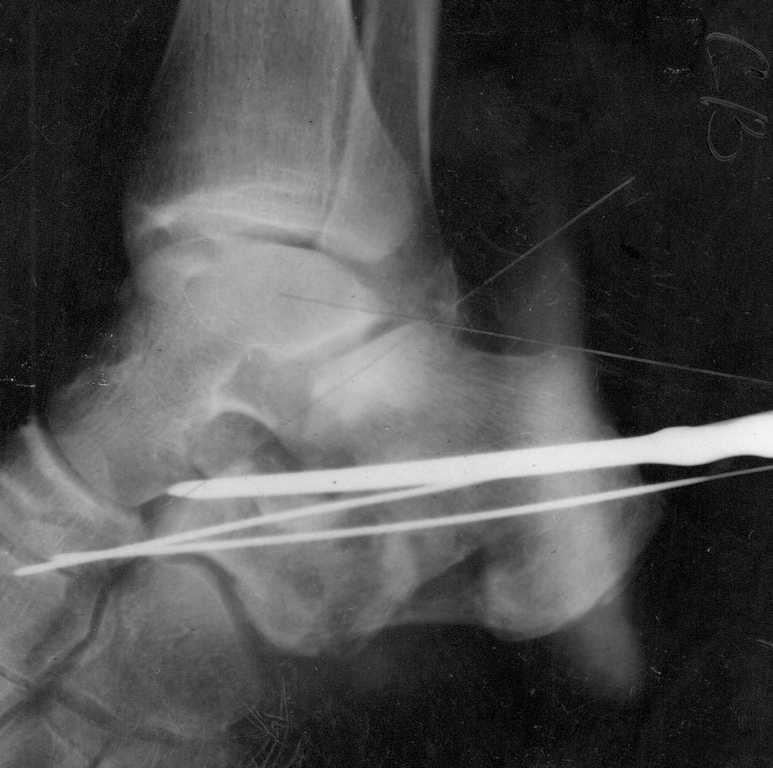

Сделали данному больному операцию. Фиксация перелома спицами. Это интраоперационный снимок.